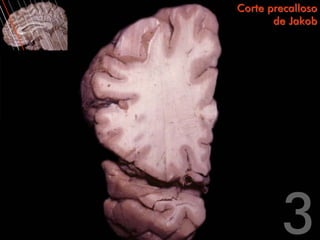

Corte precalloso

de Jakob

Circunvolución frontal superior   Corte precalloso

Surco frontal                            de Jakob

superior                                          Circunvolución

frontal medial

Circunvolución frontal

media                                                                       Surco del cíngulo

Surco frontal inferior

Circunvolución del

Circunvolución

cíngulo

frontal inferior

Centro oval del

Rodilla del

lóbulo frontal

cuerpo calloso

Circunvolución                                                              Fórceps menor

temporal superior

Surco temporal superior                                     Surco lateral

temporal media

Circunvolución frontal superior Corte precalloso Surco frontal de Jakob superior Circunvolución frontal medial Circunvolución frontal media Surco del cíngulo Surco frontal inferior Circunvolución del Circunvolución cíngulo frontal inferior Centro oval del Rodilla del lóbulo frontal cuerpo calloso Circunvolución Fórceps menor temporal superior Surco temporal superior Surco lateral Circunvolución temporal media